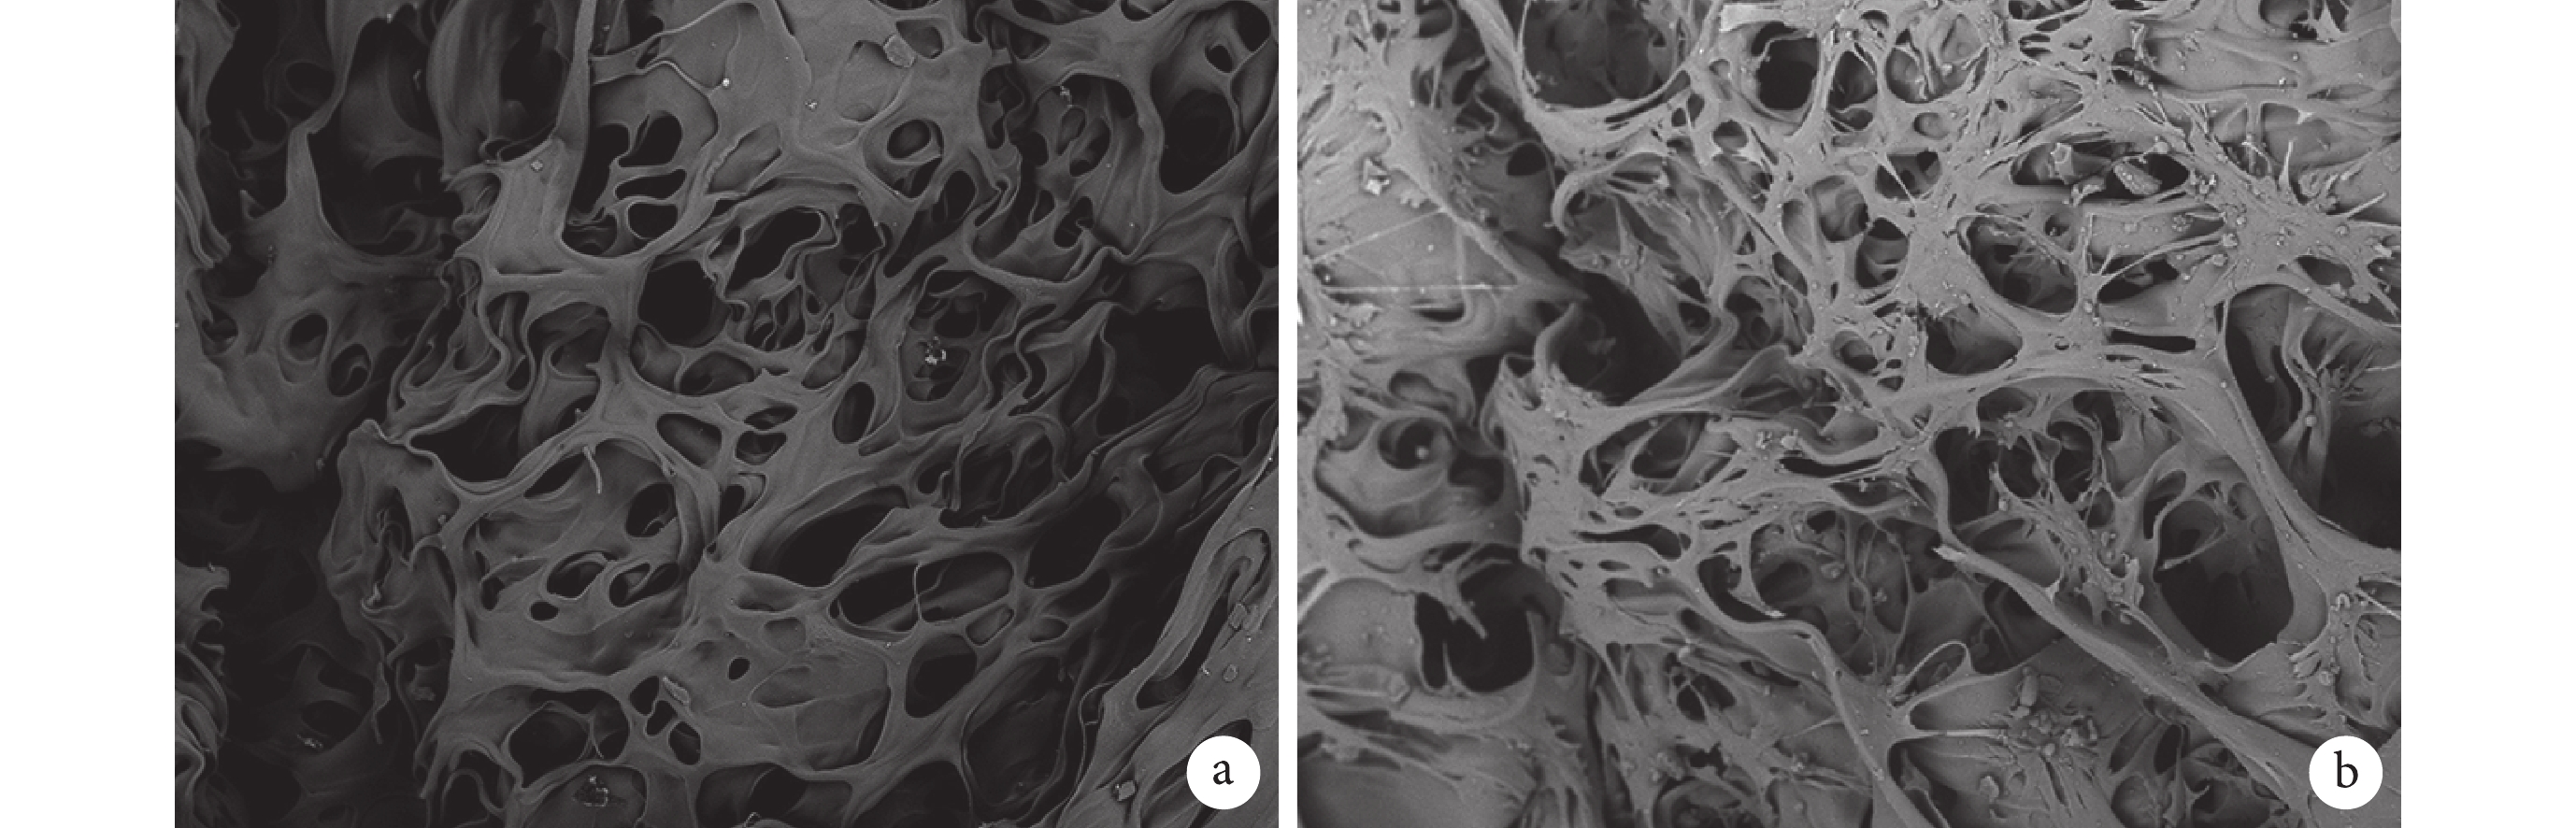

乙醇替代法檢測殼聚糖多孔支架的孔隙率為 90.0%±0.5%。掃描電鏡可見支架橫斷面內部密布大小相對均一的孔洞,孔相通性較好,孔徑為 80~200 μm,平均 140 μm。支架-細胞復合培養 48 h 掃描電鏡觀察示,BMSCs 廣泛分布于殼聚糖多孔支架表面及孔內,細胞呈梭形并分泌細胞外基質黏附于支架上,其在三維培養環境下生長良好。見圖 2。

a. 殼聚糖多孔支架;b. 支架-細胞復合培養 2 d

Figure2. Scanning electron microscope observation (×200)a. Chitosan porous scaffold; b. Scaffold-cell co-cultured for 2 days